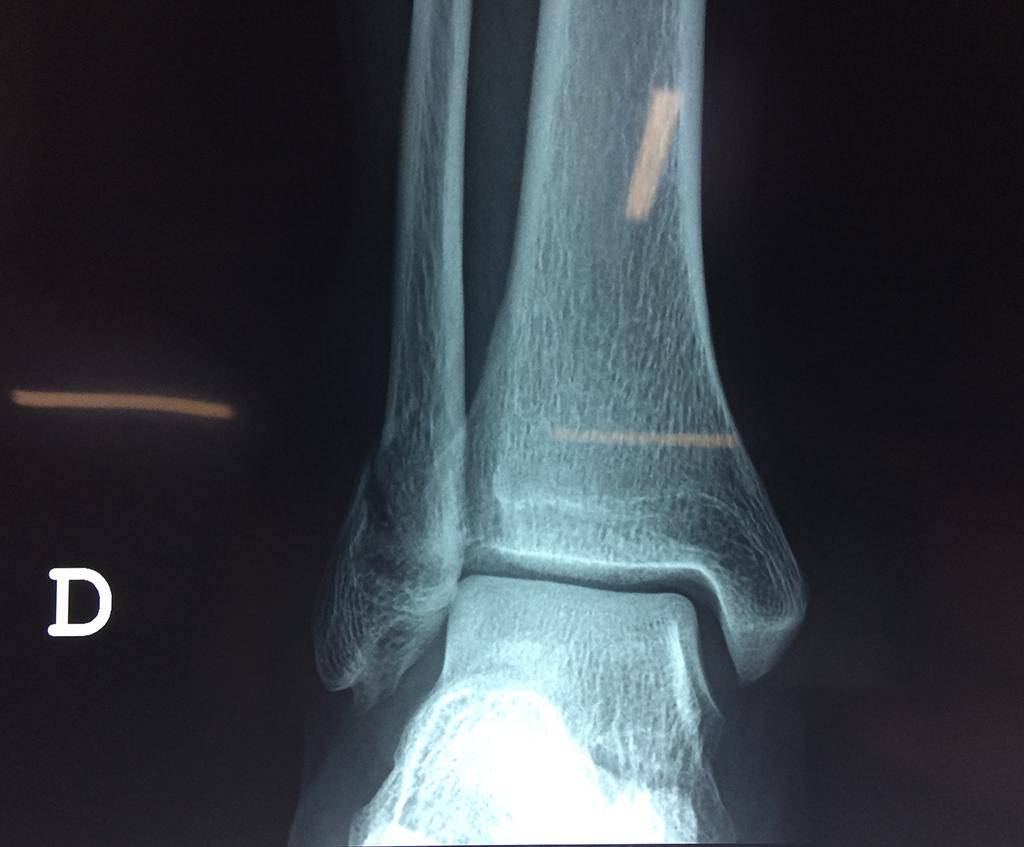

Una fractura de tobillo es la rotura de uno o más de los huesos del tobillo. Estas fracturas pueden ser:

- Los extremos de los huesos están desalineados entre sí (desplazados).

- La fractura se extiende hasta la articulación del tobillo (fractura intra-articular).